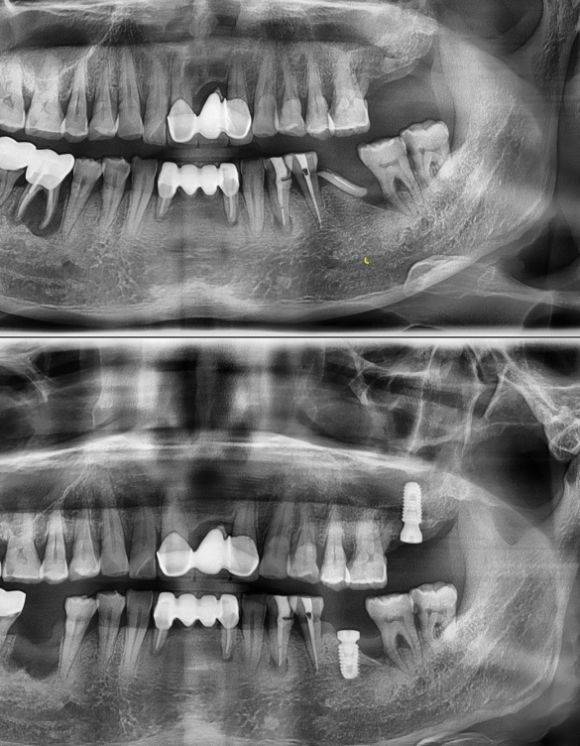

상기 환자 치아 상실된지 오래된 분으로

잔존치근 발치 후 남은 잇몸뼈를 이용하여 임플란트 수술을 진행하였습니다.

위쪽 어금니는 뼈가 매우 많이 상실된 상태로,

상악동 수술과 뼈이식을 진행하였습니다.

임플란트 수술 반대쪽 아래턱을 보시면 발치한 지 얼마 되지 않을 site를 확인하실 수 있는데

만성 뿌리주위 염증으로 인한 뼈의 소실이 매우 심한 상태로

복잡한 뼈이식을 통한 잇몸뼈를 만드는데 상당한 노력과 시간이 필요할 것 같습니다.